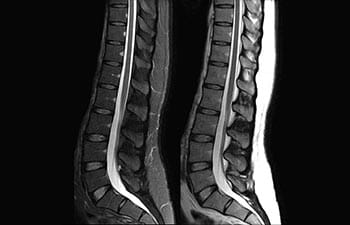

Conozca cómo Ingenia Prodiva puede satisfacer sus necesidades clínicas.

Conozca la opinión de los primeros usuarios de Ingenia Prodiva 1.5T acerca de sus experiencias con el sistema y cómo influye este en su centro de diagnóstico por imagen.